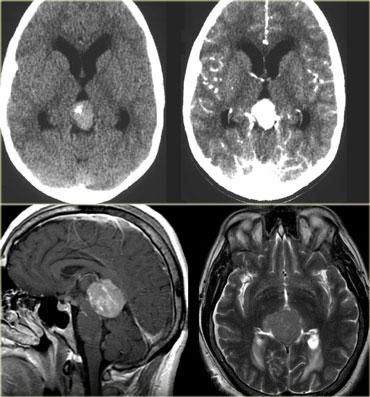

Ngấm thuốc dạng vòng

Ngấm thuốc dạng vòng được thấy trong di căn não và u thần kinh đệm độ cao.

Nó cũng được thấy trong các tổn thương không phải u như áp xe, một số mảng xơ cứng rải rác (MS) và đôi khi trong khối máu tụ cũ.

Bên trái là ba tổn thương ngấm thuốc dạng vòng khác nhau.